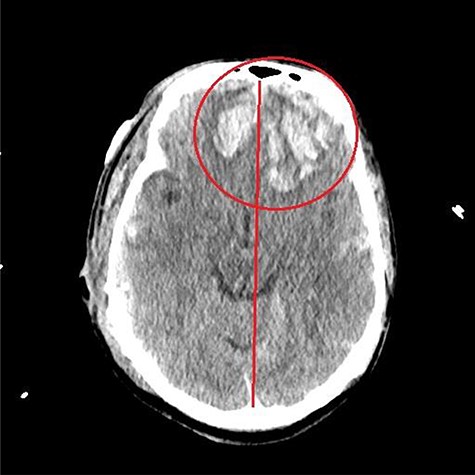

He had a significant recovery, to the point where he was awake with mild right paresis. He was following commands briskly but remained nonverbal. On hospital day 26, he developed neurological deterioration with decreased mental status and worsening right hemiparesis. Clinical examination noted pronounced new indentation of his hemicraniectomy flap site. CT head showed a rightward shift away from the craniectomy site and impending herniation (Fig. 4).

CT head POD26 from craniectomy demonstrating findings consistent with SSFS.

He was positioned in Trendelenburg position and infused with intravenous fluids with some improvement in his symptoms. Based on his clinical and radiographic picture, SSFS was suspected. He was taken to the operating room for an emergency left cranioplasty, with a preformed fronto-temporo-parietal titanium mesh.